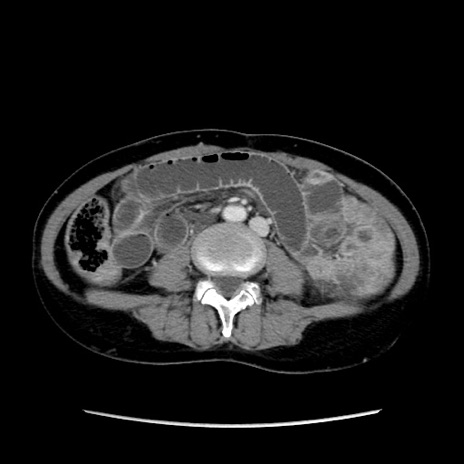

症例32(横断像)

【症例】40歳代 女性

【主訴】上腹部痛、嘔気・嘔吐

【現病歴】約9時間前頃から急に上腹部痛、嘔気、嘔吐が出現。改善しないため救急要請。

【既往歴】子宮頚癌(広汎子宮全摘術、放射線療法)、腸閉塞

【身体所見】腹部:平坦、軟、腸雑音亢進、上腹部を中心に腹部全体に圧痛あり。

【データ】WBC 8400、CRP 0.03